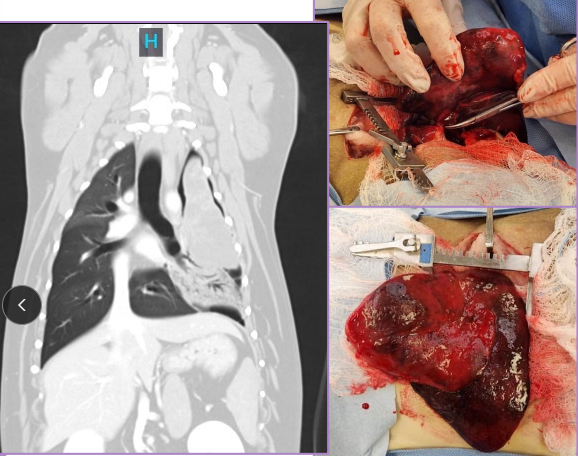

Splenic Neoplasia

Et: VERY common!

Non-neoplastic: hematoma, lipoma, myelolipoma

Benign: hemangioma, fibroma

Malignant: hemangiosarcoma HSA (#1), fibrosarcoma, liposarcoma, MCT

Sig: Lg-breed dogs

Cs: shock, mass, enlarged abdomen, fluid wave, lethargy, pain, vomiting, PCV on free fluid - determine blood, VPCs

Dt: Abd rads (mass effect, effusion, metastasis), US (mixed echotexture, cavitated lesions, enlarged spleen), biopsy

Xray chest for mets!

Tx: splenectomy

Splenectomy: Neoplasia, trauma, IM dz

Classic: dissect & ligate/divide all hilar vessels; protect short gastric a.

Alternate: Abdominal exploration, isolate, ligate splenic a. & v. distal to pancreatic branch/short gastric aa. / L gastroepiploic

quicker, best for no adhesions